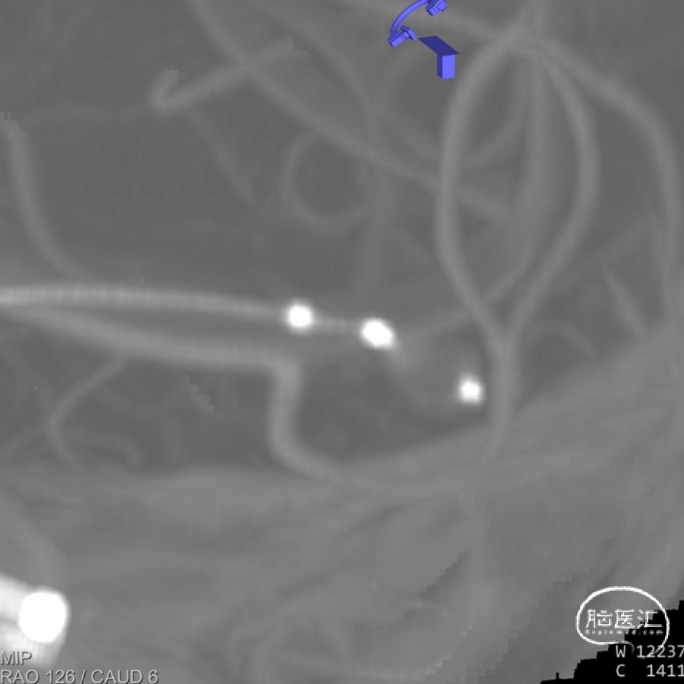

沿微导管缓慢推送WEB™,直至WEB™完全释放占据整个瘤腔。

释放后Dyna CT。

释放后造影显示WEB™打开完全,贴壁良好,对载瘤动脉血流无甚影响,解脱WEB™,术毕。

术后造影显示动脉瘤内造影剂滞留,载瘤动脉通畅,栓塞效果良好。